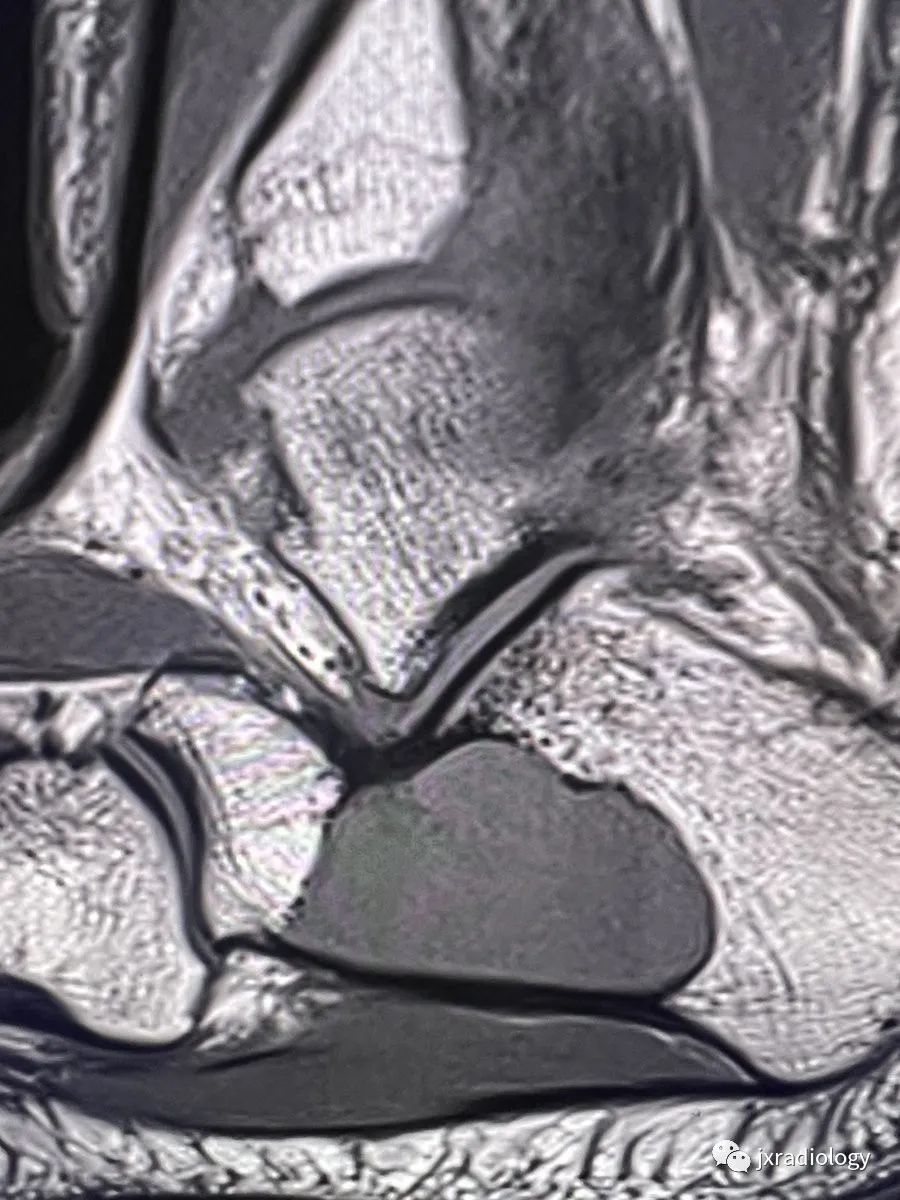

以下是踝关节磁共振显示的跟骨囊肿: